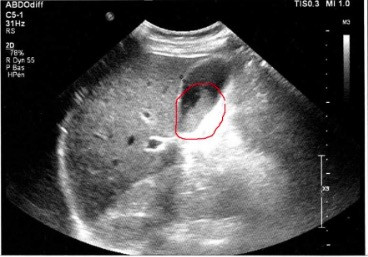

Voir les images.

Examen échographique : ci dessous, je montre 2 images d'échographie avant et après nettoyage de la vésicule biliaire, confirmant qu'il y a eu expulsion des calculs biliaires grâce à la cure d'Andreas Moritz. Ces images sont tirées des témoignages de personnes ayant pratiqué cette cure.

- Vous faîtes une échographie de contrôle juste après la cure : la vésicule ne contient plus de calculs ou en contient moins. Le médecin en profite pour vérifier la paroi de la vésicule.